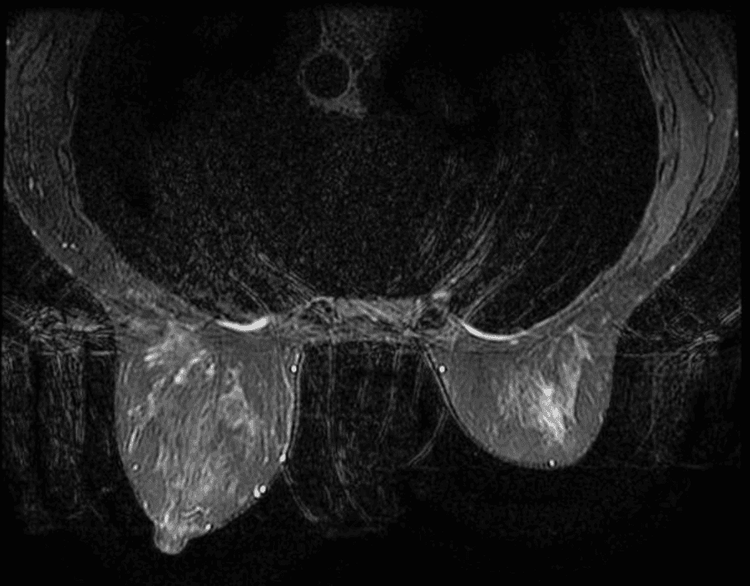

Cộng hưởng từ vú là kỹ thuật hình ảnh sử dụng từ trường, sóng vô tuyến và máy tính để tạo ra các hình ảnh chi tiết về tuyến vú. Đây là kỹ thuật giúp sàng lọc, chẩn đoán và theo dõi điều trị các bệnh lý tuyến vú.

Chụp cộng hưởng từ tuyến vú sẽ giúp:

- Tầm soát ung thư vú (Phần I) ở nhóm phụ nữ có nguy cơ cao.

- Đánh giá lan rộng ung thư vú trước điều trị.

- Đánh giá chi tiết hơn các bất thường chưa rõ trên nhũ ảnh và/hoặc siêu âm vú.

- Theo dõi sau phẫu thuật u vú.

- Đánh giá đáp ứng sau điều trị hóa/xạ trị u vú.

- Là phương tiện hình ảnh tốt trong đánh giá biến chứng rách vỡ túi ngực.